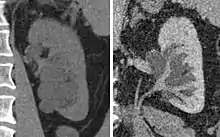

Renal ultrasonography of hydronephrosis caused by a left ureteral stone.